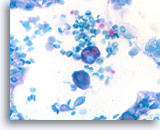

Figure 166

Cryptococcus

Multiple intracellular yeasts are seen within the cytoplasm of macrophages in Cryptococcus infection.

Cryptococcus

Multiple intracellular yeasts are seen within the cytoplasm of macrophages in Cryptococcus infection.

Figure 166

Cryptococcus

Multiple intracellular yeasts are seen within the cytoplasm of macrophages in Cryptococcus infection.

Cryptococcus

Multiple intracellular yeasts are seen within the cytoplasm of macrophages in Cryptococcus infection.